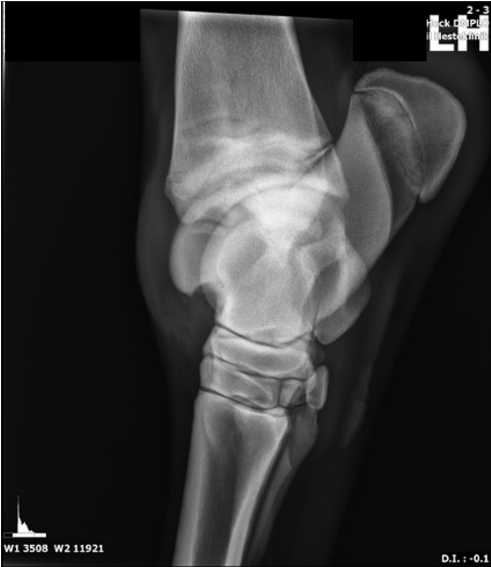

På dette røntgenbillede findes osteochondrose på et prædilektionssted i talocruralleddet hos hest. Hvilke andre prædilektionssteder for osteochondrose i talocruralleddet hos hest findes der?

1 Laterale trochlea, mediale malleol

2 Distale intermediærkam af tibia, laterale trochlea

3 Mediale kondyl, mediale malleol

4 Tuberositas tibia, distale intermediærkam

Det rigtige svar er 1